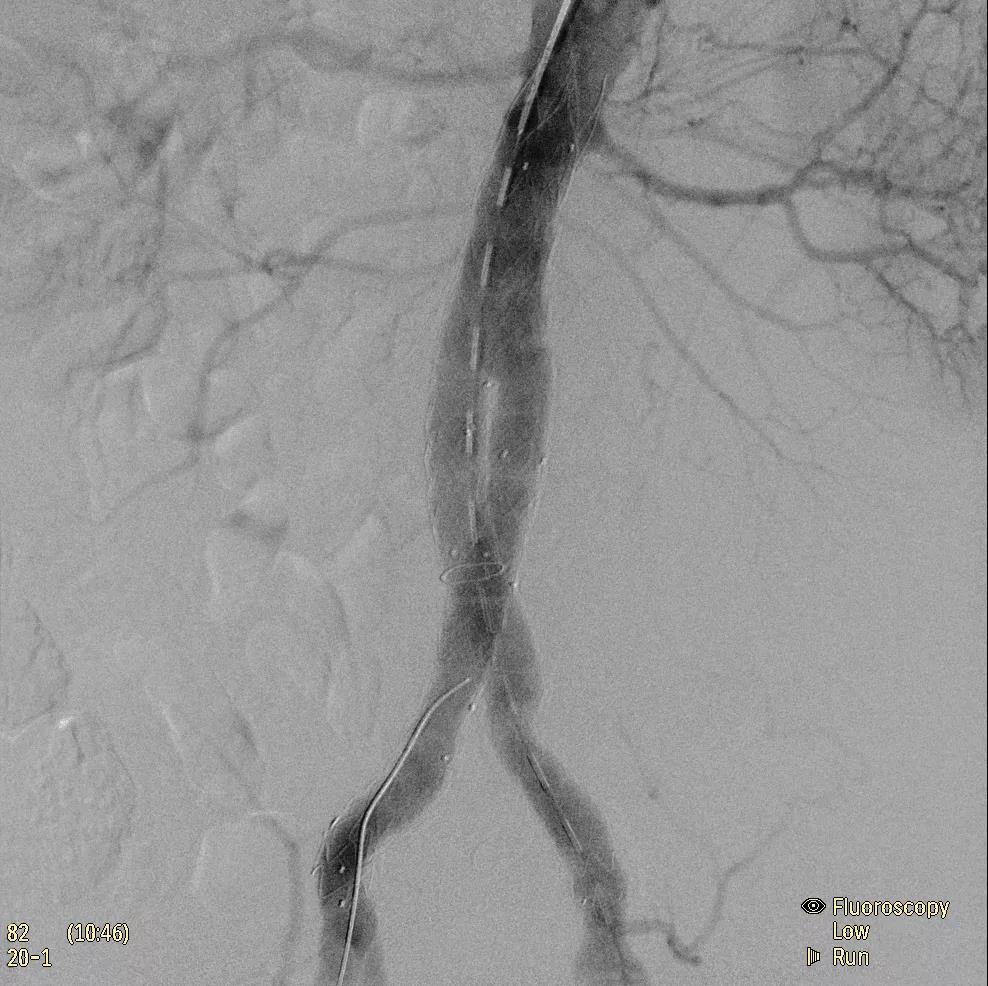

飛利浦于2019年2月18日宣布推出帶扁平探測(cè)器的移動(dòng)式C臂Zenition 70。Zenition 70使用飛利浦第四代Flat Detector系統(tǒng),具有卓越的成像清晰度和靈活性,可執(zhí)行各種情況。

據(jù)器械之家了解到,移動(dòng)式C型臂是X射線系統(tǒng),可帶入手術(shù)室(OR),在整形外科、創(chuàng)傷和血管手術(shù)等各種手術(shù)過(guò)程中提供實(shí)時(shí)圖像引導(dǎo)。Zenition70使醫(yī)院能夠最大限度地提高OR性能,增強(qiáng)臨床能力并為員工提供高質(zhì)量的用戶體驗(yàn)。

( Zenition 70匯集了圖像捕獲,圖像處理,易用性和多功能性方面的創(chuàng)新。)

在快速增長(zhǎng)的圖像引導(dǎo)微創(chuàng)手術(shù)領(lǐng)域 ,手術(shù)干預(yù)的范圍和復(fù)雜性在繼續(xù)增加,需要治療的患者數(shù)量也在增加。為了以更低的成本治療更多的患者,醫(yī)院需要具有不同能力的多功能C臂組,以便容易地適應(yīng)不同類型的手術(shù)和不同操作者的需要。Zenition 70易于在手術(shù)室之間移動(dòng),易于在患者周圍定位并且操作直觀。

飛利浦Zenition 70支持整個(gè)醫(yī)療保健機(jī)構(gòu)提高OR性能。平臺(tái)類似平板電腦的用戶界面和簡(jiǎn)單的統(tǒng)一工作流程意味著一旦操作員學(xué)會(huì)在平臺(tái)上使用一個(gè)系統(tǒng),他們就可以輕松地操作它們。該系統(tǒng)可在任何介入或外科手術(shù)過(guò)程中快速直觀地拍攝傻瓜相機(jī)。Zenition的緊湊設(shè)計(jì),位置記憶功能(僅適用于Zenition 70)和BodySmart軟件,即使在圖像增強(qiáng)器或平板探測(cè)器的邊緣也能捕捉快速一致的圖像,將C臂重新定位的需求減少45%。

( Zenition 70采用與Azurion平臺(tái)相同的圖像處理算法。

為了獲得清晰的高質(zhì)量圖像,Zenition 70 采用了與公司Azurion平臺(tái)相同的圖像處理算法,可提供患者解剖結(jié)構(gòu)的高清可視化和更大的可視區(qū)域。飛利浦的MetalSmart軟件等功能可確保圖像質(zhì)量,該軟件可自動(dòng)調(diào)整圖像的對(duì)比度和亮度,以便在視野中存在金屬物體(如植入物)時(shí)提高圖像質(zhì)量 - 這一特性使Zenition 70在整形外科中特別有用。